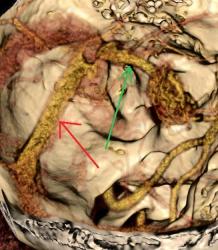

Виден клубок неправильно развитых сосудов, питающихся от задней мозговой артерии и дренирующийся в прямой синус. Перифокальных изменений нет.

Черная стрелка - питащий сосуд - задняя мозговая артерия, зеленая - дренирующая вена к прямому синусу, красная - прямой синус.

Я чуть увеличил фрагменты изображений с "патологическим состоянием"

Очень наглядна видна сосудистая мальформация.

Питание идет из гипертрофированных задней мозговой и средней мозговой артерий (красные стрелки), дренирование в основном в верхний сагиттальный синус (синий кружок). Дренирующая вена - синие стрелки.